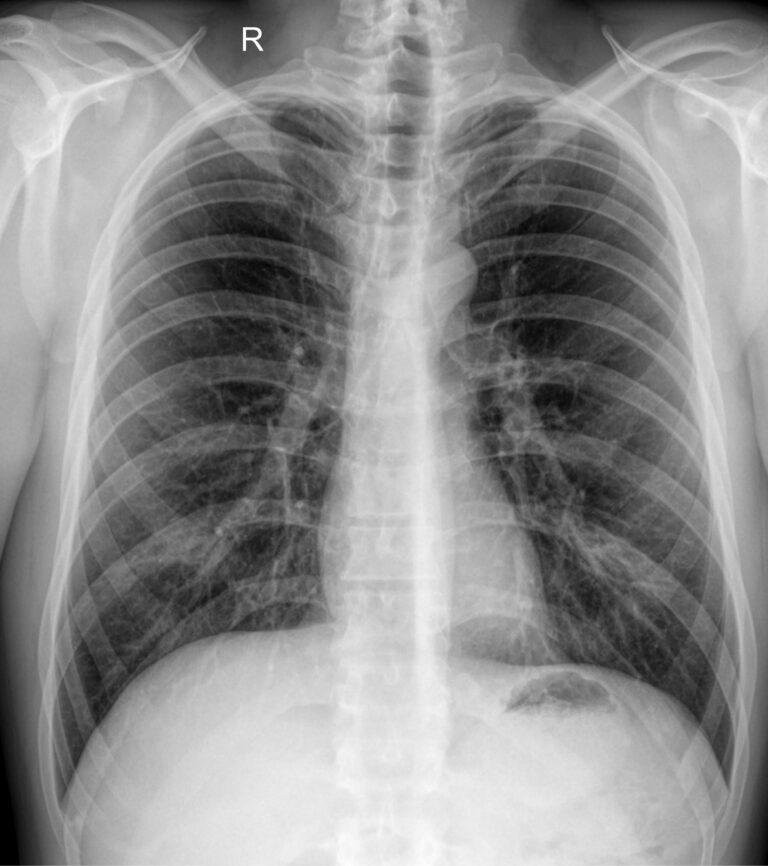

Флюорография (ФЛГ) ― это скрининговый метод выявления изменений в легких. В основном ее используют для диагностики туберкулеза и онкологических заболеваний. Метод основан на свойстве рентгеновских лучей проходить сквозь органы и ткани человека, в большей или меньшей степени поглощаясь ими. От обычного рентгена грудной клетки флюорография отличается уменьшенными размерами изображения, меньшей стоимостью, а также целями: ФЛГ применяют в качестве диагностики у внешне здоровых людей, даже не имеющих жалоб.

В нашей клинике для проведения флюорографии мы применяем классическую цифровую рентгенографию органов грудной клетки, что позволяет сократить лучевую нагрузку и увеличить качество изображения при сохранении низкой стоимости исследования.

• Здоровую грудную клетку, о чем в заключении будет стоять соответствующая запись: «Органы грудной клетки без патологии» или «Изменений не выявлено».

• Очаговые затемнения. В этих случаях описывается их местоположение и размеры;

• Также на ФЛГ-снимке можно увидеть повышенную прозрачность легочной ткани, массивные рубцовые и фиброзные изменения, сросшиеся переломы, инородные тела.

Непосредственно результат флюорографии не является окончательным диагнозом. Все заключения рентгенолога интерпретируются лечащим врачом, с использованием дополнительных методов диагностики.